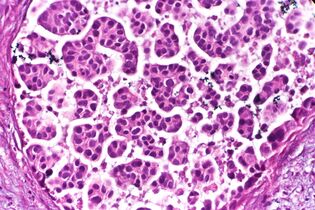

The most commonly used stain in histology is a combination of hematoxylin and eosin (often abbreviated H&E). Hematoxylin is used to stain nuclei blue, while eosin stains the cytoplasm and the extracellular connective tissue matrix of most cells pink. There are hundreds of various other techniques which have been used to selectively stain cells. Other compounds used to color tissue sections include safranin, Oil Red O, congo red, silver salts and artificial dyes. Histochemistry refers to the science of using chemical reactions between laboratory chemicals and components within tissue. A commonly performed histochemical technique is the Perls' Prussian blue reaction, used to demonstrate iron deposits in diseases like Hemochromatosis.[2]

Recently, antibodies have been used to stain particular proteins, lipids and carbohydrates. Called immunohistochemistry, this technique has greatly increased the ability to specifically identify categories of cells under a microscope. Other advanced techniques include in situ hybridization to identify specific DNA or RNA molecules. These antibody staining methods often require the use of frozen section histology. These procedures above are also carried out in the laboratory under scrutiny and precision by a trained specialist medical laboratory scientist (a histoscientist). Digital cameras are increasingly used to capture histopathological images.